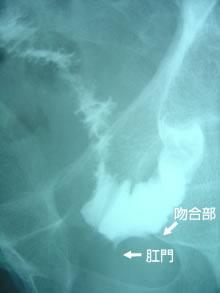

術中写真 1

肛門のすぐ口側に直腸がんによる狭窄像を認めます。

術中写真 2

直腸切除後に肛門とS状結腸との吻合を行いました。